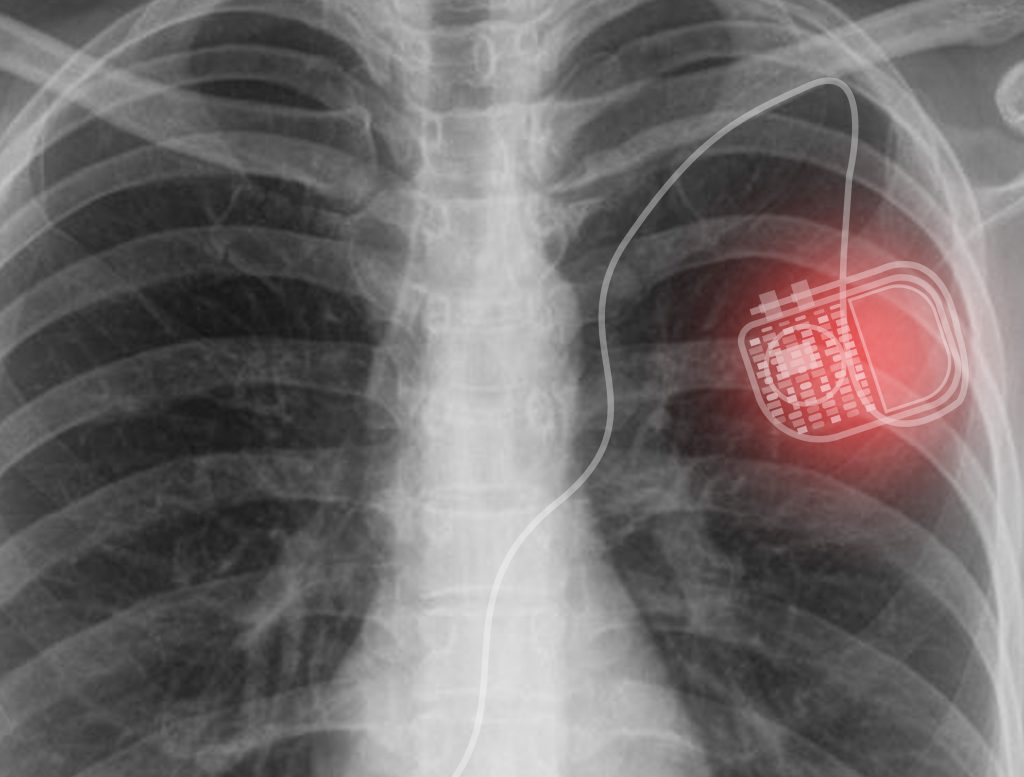

Pacemakers And Defibrillators Frequently Asked Questions . Do icds need to be adjusted? Do cell phones interfere with pacemakers? If you think you may have a medical emergency, immediately call your doctor or dial 911. The good news is that medtronic pacemakers and implantable defibrillators (icds) have built in features that protect them from many types of. Here are answers to these and other questions. Controls the heartbeat by delivering shocks to the heart when the device detects an irregular heartbeat. Faqs about pacemakers and implantable cardioverter defibrillators (icds) do cell phones or electronic devices interfere with pacemakers or. Pacemaker implantation is a relatively common heart procedure. Defibrillators deliver a shock if the heart goes into arrhythmia. Defibrillators and pacemakers help the heart maintain a regular rhythm. Discover two inspiring stories of life with a pacemaker.